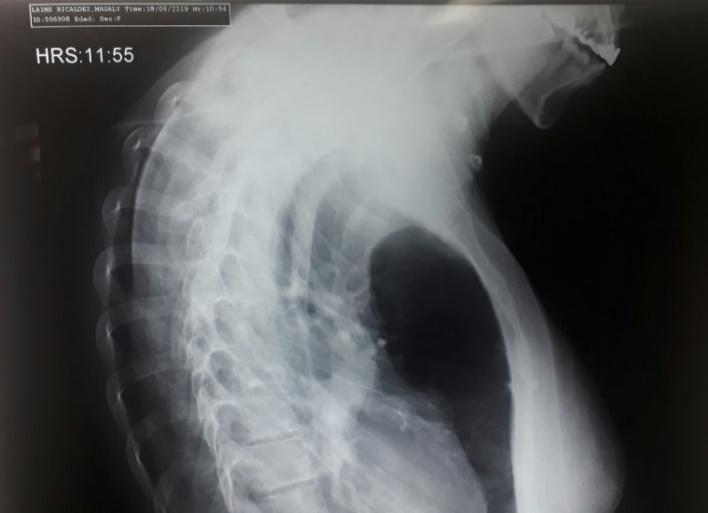

Hipertensión pulmonar severa y embarazo. reporte de un caso clínico

Severe pulmonary hypertension and pregnancy. report of a clinical case

Choquecallata, Walter Andrés Terceros,..........................................................................................68-73 Carta al Editor